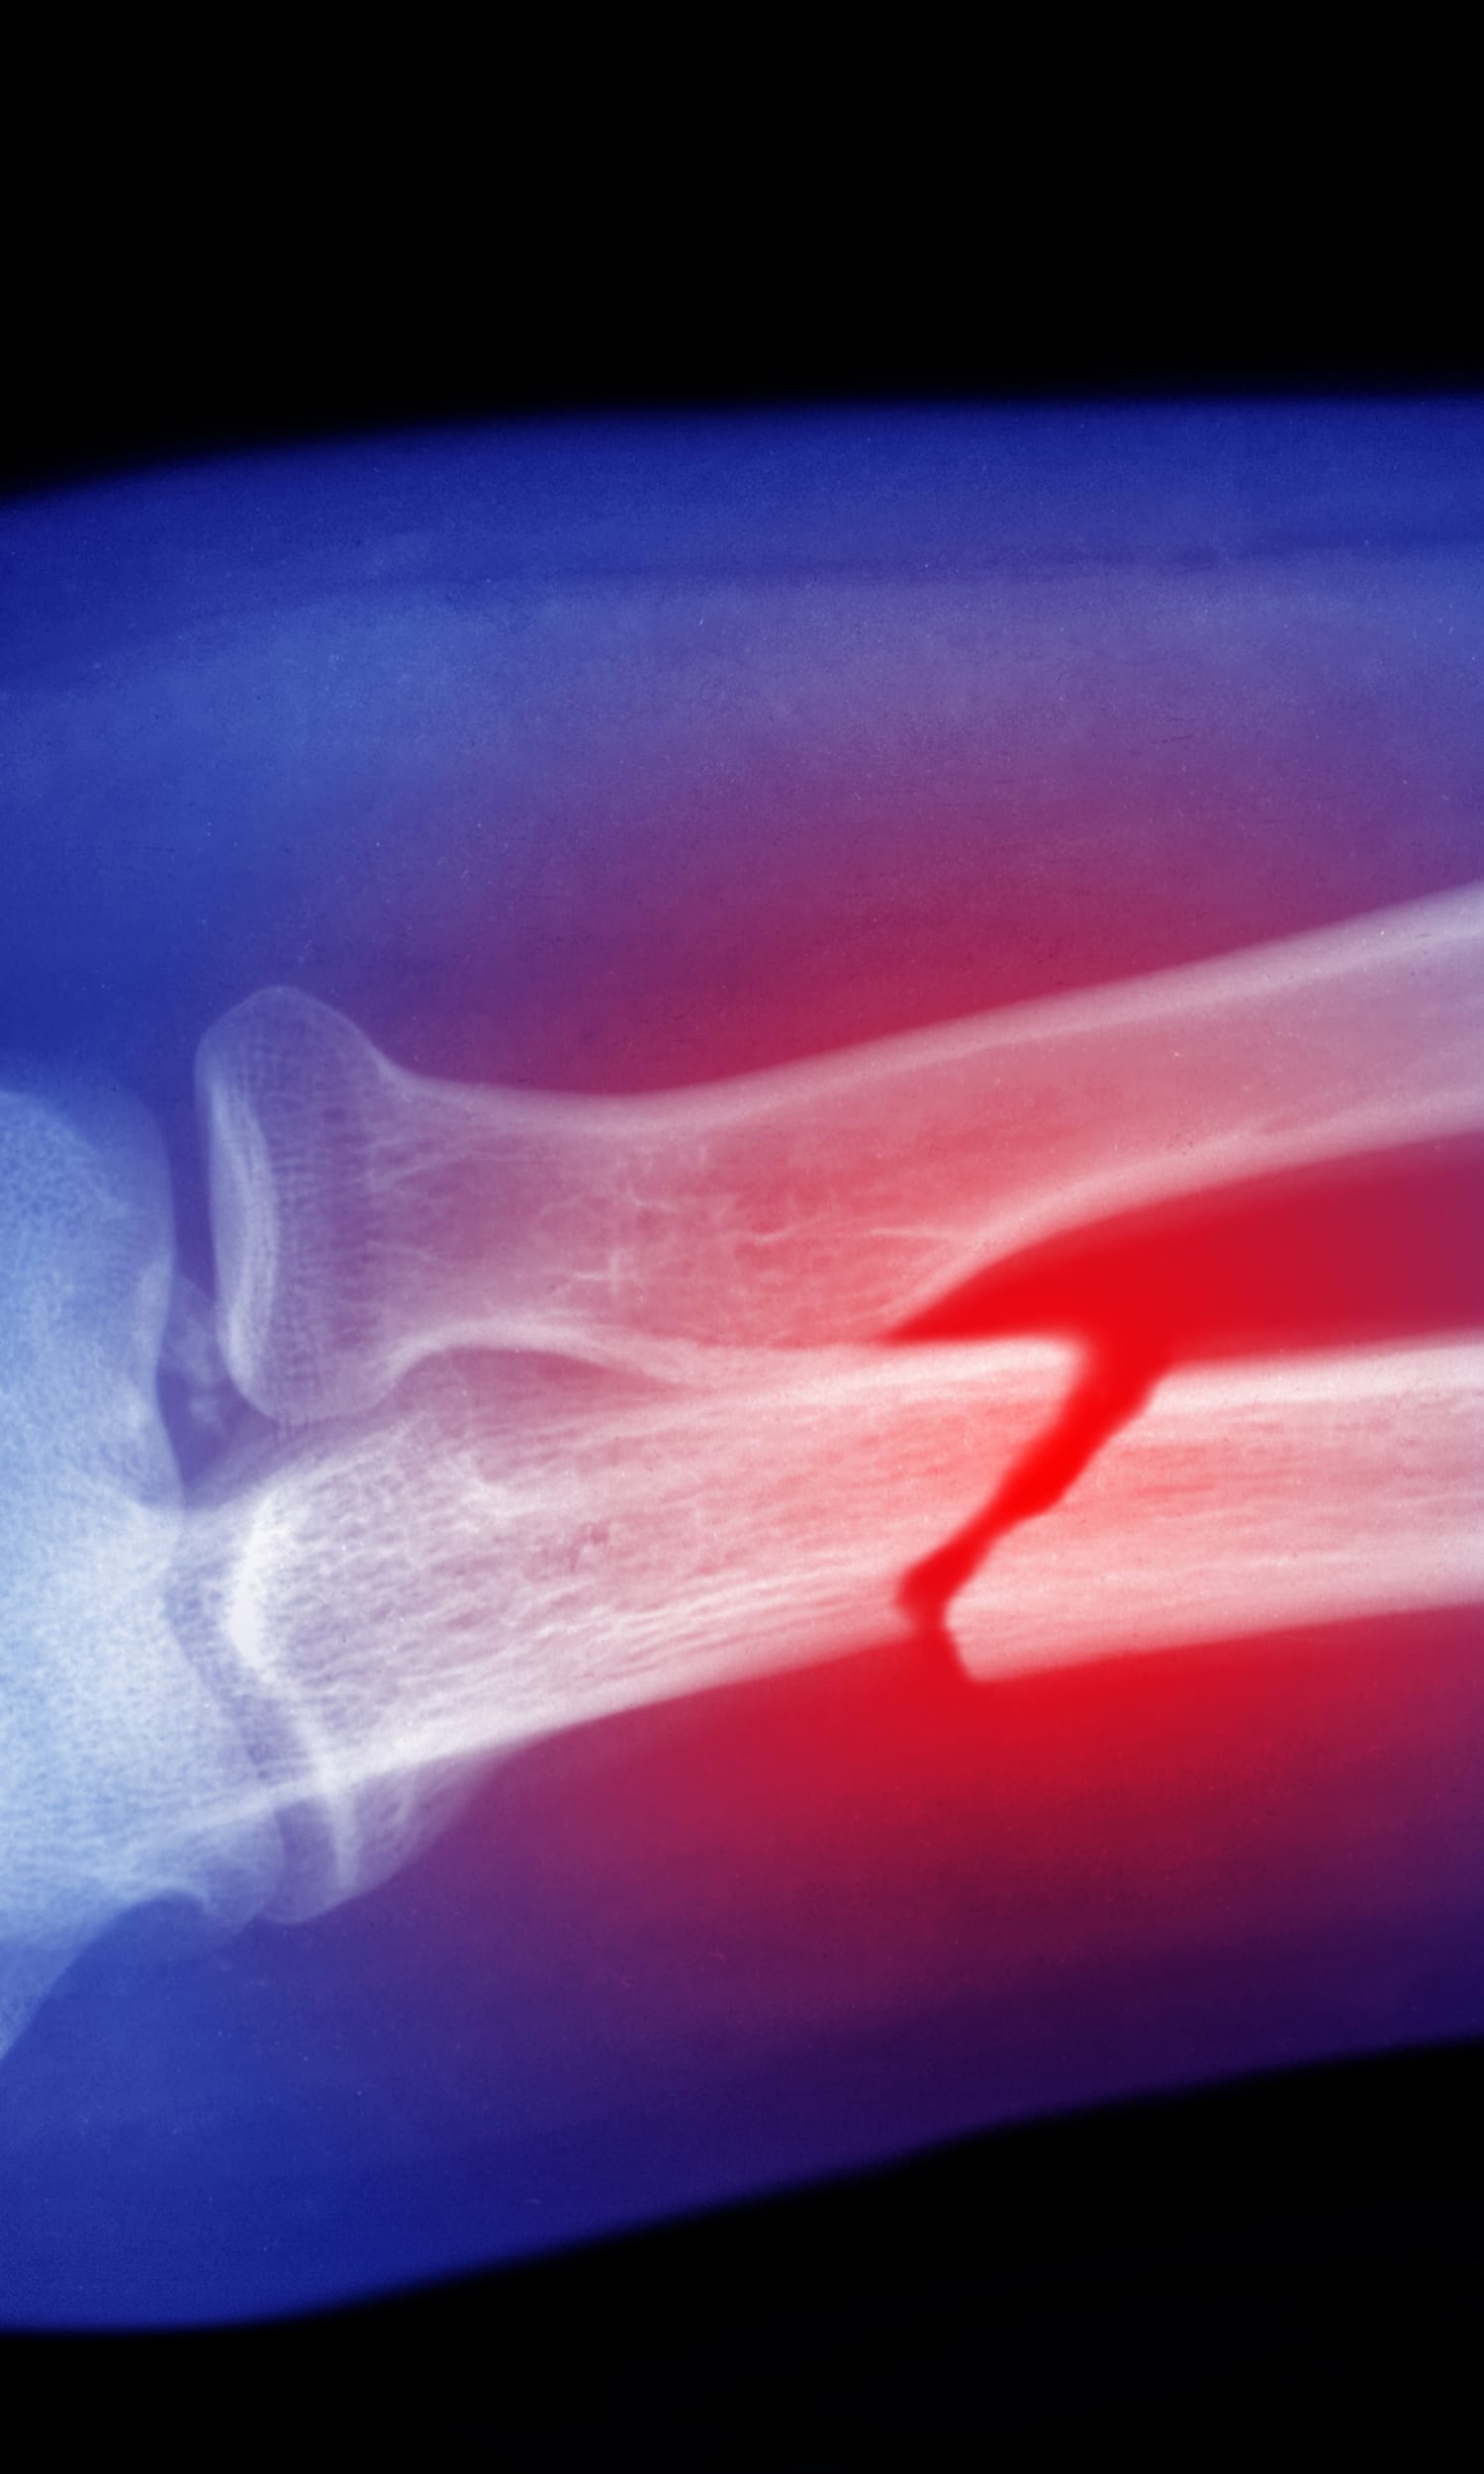

• Trauma care for all trauma patients admitted to Yale New Haven Hospital, the regional Level 1 trauma center for southern Connecticut and the only trauma center in the state to be verified by the American College of Surgeons for both adult and pediatric patients.